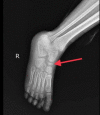

Kohler's disease is characterized by osteochondritis of the navicular bone due to various factors like the lack of blood supply and late ossification of the bone. In particular, it is a disease of the pediatric age group, which has male preponderance. It may present with bony pain unilaterally or, at times, be asymptomatic and diagnosed accidentally. Clinical presentation and radiological investigations are the mainstay of diagnosis. This self-limiting condition requires only symptomatic conservative management. A surgical approach is not yet indicated. One such case of bilateral Kohler's disease is presented in this report. Here, we discuss the disease's presentation, examination, treatment, and prognosis.